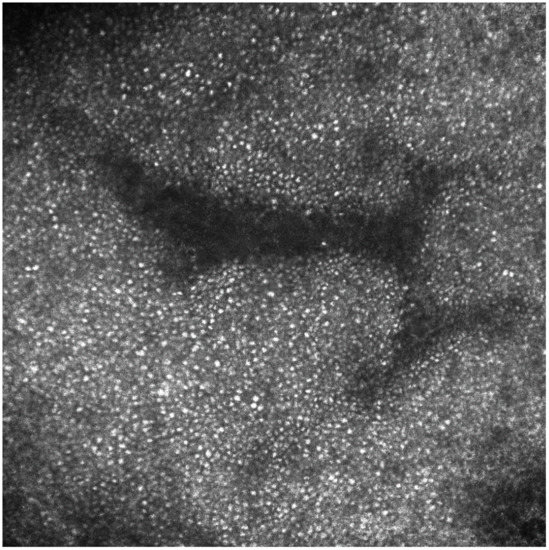

Slit-lamp bio-microscopy examination of the cornea showed whorl-like lines in the inferior cornea of both eyes. With a suspicion of FD, HH-RCM examination was performed after local anesthesia in order to find a corneal overload. RCM revealed the presence of intracellular hyper-reflective inclusions in most of the epithelial cells (Figure 3), which can possibly be related to deposition and accumulation of glycosphingolipids.

Figure 3.

Reflectance confocal microscopy reveals the presence of intracellular hyper-reflective inclusions in most of the epithelial cells of the cornea related to deposition and accumulation of glycosphingolipids.

Having a prevalence of up to 95%, CV is the most common and early ocular signs of FD [1,2,3]. Differential diagnoses include other diseases causing CV, such as lipidosis, sphingolipidosis, mucopolysaccaridosis and endothelial congenital hereditary dystrophy [3]. To the best of our knowledge, no data are available on the RCM corneal aspect of patients with other endogenous storage diseases associated with CV. However, the main cause of CV encountered in routine clinical practice is the ingestion of amphiphilic drugs, predominantly amiodarone [2]. Although amiodarone keratopathy does not differ from FD-induced CV on slit-lamp microscopy as both diseases form vortex keratopathy, it is reported in medical literature that RCM can reveal morphological differences between FD and amiodarone-induced keratopathy in most patients. Lower hyper-reflectivity, homogeneous size of the deposits and a diffuse pattern serve to differentiate sphingolipid accumulation from amiodarone keratopathy under RCM [3,4]. Our case confirmed these features since we found a diffuse hyper-reflection of all the epithelial cells of the cornea with a hyper-reflectivity that was less intense than the one identified in the case of drug-induced CV.